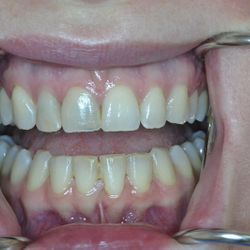

Η νεαρή αυτή ασθενής μας είχε ολοκληρώσει παλαιότερη ορθοδοντική θεραπεία, η οποία είχε οδηγήσει σε νέκρωση τον άνω δεξιό κεντρικό και πλάγιο τομέα.

Τα δόντια αυτά είχαν απονευρωθεί στο παρελθόν και είχαν μαυρίσει.

Τοποθετήθηκαν άξονες υαλονημάτων (ParaPost FiberWhite/Coltene) για ενίσχυση των ριζών και στη συνέχεια χτίστηκαν όψεις ρητίνης (Herculite XVR Ultra/Kerr) για να διορθωθεί η δυσχρωμία τους.